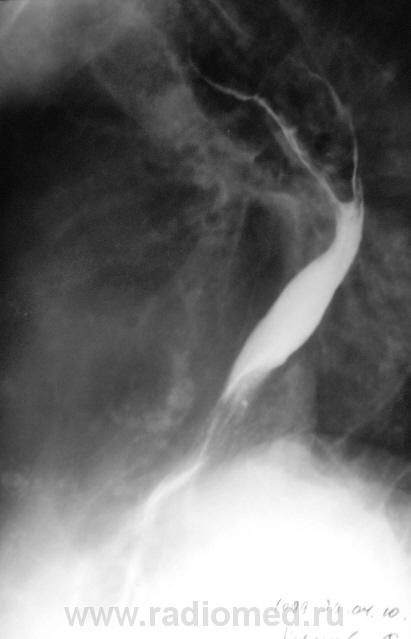

Пациентка, весьма преклонного возраста направлена на исследование желудка. Диагноз - язвенная болезнь желудка. Ну с желудком вроде-бы нормально, но вот с пищеводом возникли заморочки. Все осложнилось еще и тем, что пациентка в вертикальном положении смогла побыть секунд 40.

Ниже снимки, которые смогли провести в положении стоя.

ахалазия пищевода...

Похоже что в нижней трети пишевода чтото "живёт"

Озлокачествленная лейомиома пищевода.